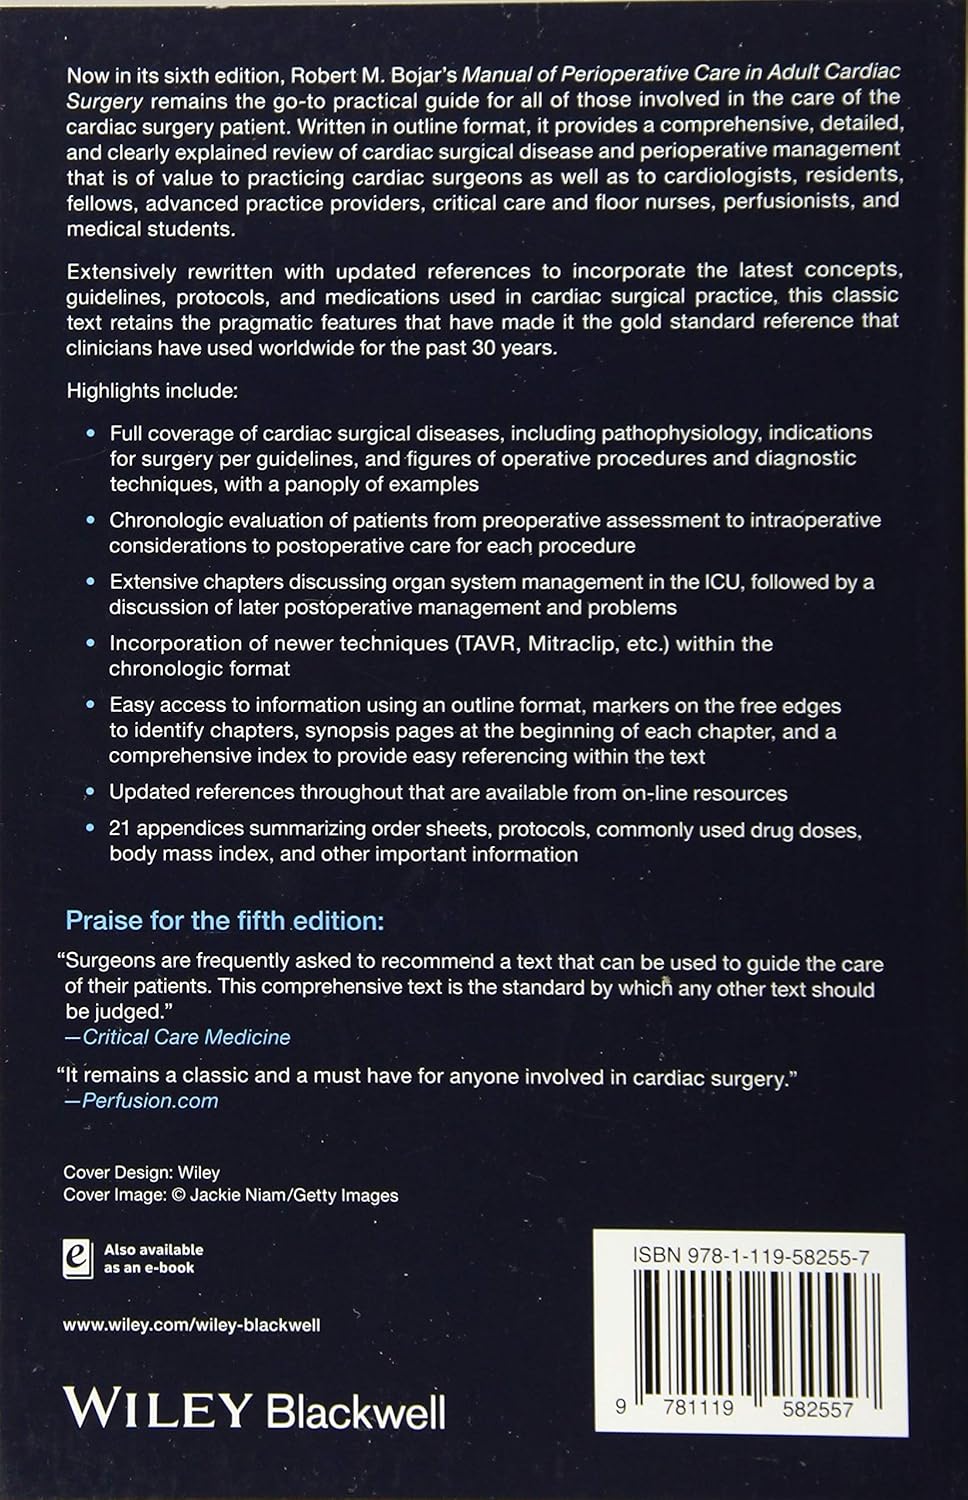

Now in its sixth edition, Robert M. Bojar’s Manual of Perioperative Care in Adult Cardiac Surgery remains the go-to practical guide for all of those involved in the care of the cardiac surgery patient. Written in outline format, it provides a comprehensive, detailed, and clearly explained review of cardiac surgical disease and perioperative management that is of value to practicing cardiac surgeons as well as to cardiologists, residents, fellows, advanced practice providers, critical care and floor nurses, perfusionists, and medical students.

Extensively rewritten with updated references to incorporate the latest concepts, guidelines, protocols, and medications used in cardiac surgical practice, this classic text retains the pragmatic features that have made it the gold standard reference that clinicians have used worldwide for the past 30 years.

Highlights include:

- Full coverage of cardiac surgical diseases, including pathophysiology, indications for surgery per guidelines, and figures of operative procedures and diagnostic techniques, with a panoply of examples

- Chronologic evaluation of patients from preoperative assessment to intraoperative considerations to postoperative care for each procedure

- Extensive chapters discussing organ system management in the ICU, followed by a discussion of later postoperative management and problems

- Incorporation of newer techniques (TAVR, Mitraclip, etc.) within the chronologic format

- Easy access to information using an outline format, markers on the free edges to identify chapters, synopsis pages at the beginning of each chapter, and a comprehensive index to provide easy referencing within the text

- Updated references throughout that are available from on-line resources

- 21 appendices summarizing order sheets, protocols, commonly used drug doses, body mass index, and other important information

Praise for the fifth edition:

“Surgeons are frequently asked to recommend a text that can be used to guide the care of their patients. This comprehensive text is the standard by which any other text should be judged.”

―Critical Care Medicine

“It remains a classic and a must have for anyone involved in cardiac surgery.”

―Perfusion.com